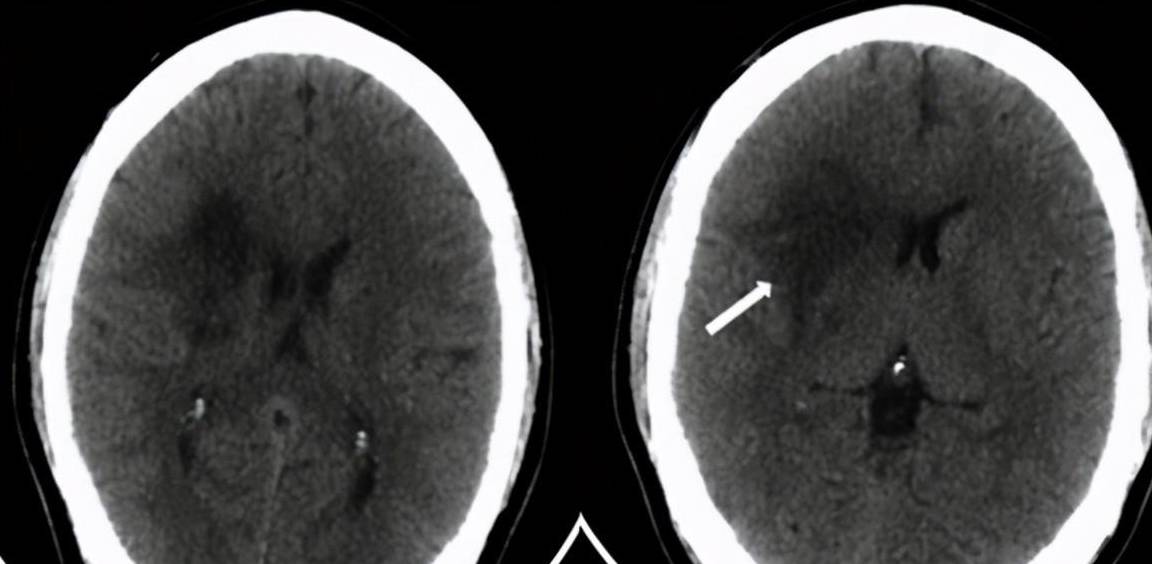

三偏综合征示意图"一侧内囊发生病变时(如本起病例卢先生的脑出血)

大脑解剖功能 一侧内囊损伤,产生 "三偏" 症状: 1

三偏征 – 病变对侧肢体偏瘫 – 病变对侧肢体感觉障碍 – 病变对侧